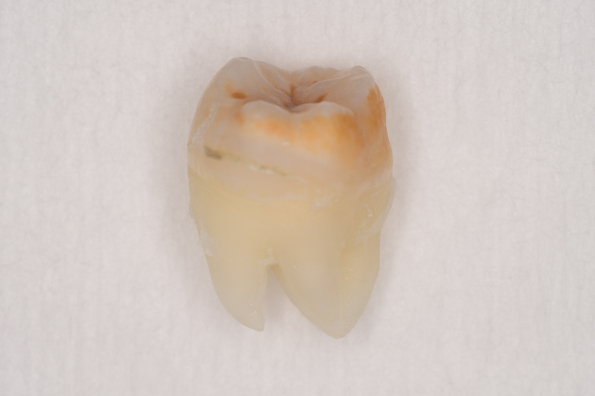

CASE 3

| 年齢・性別 | 20代・男性 |

|---|---|

| 主訴 | 左下親知らず抜きたい |

| 親知らずのはえ方 | 半埋伏 |

| 抜歯期間 | 30分 |

| 抜歯費用 | 約2,500円(保険内) 別途CT撮影で3,000円 |

| 抜歯内容 | 左下の半埋伏親知らず抜歯 |